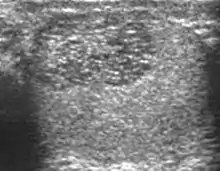

Patients with testicular lymphoma are usually old aged around 60 years of age, present with painless testicular enlargement and less commonly with other systemic symptoms such as weight loss, anorexia, fever and weakness. Bilateral testicle involvements are common and occur in 8.5% to 18% of cases. At sonography, most lymphomas are homogeneous and diffusely replace the testis [Fig. 7]. However focal hypoechoic lesions can occur, hemorrhage and necrosis are rare. At times, the sonographic appearance of lymphoma is indistinguishable from that of the germ cell tumors [Fig. 8], then the patient's age at presentation, symptoms, and medical history, as well as multiplicity and bilaterality of the lesions, are all important factors in making the appropriate diagnosis.

Primary leukemia of the testis is rare. However, due to the presence of blood-testis barrier, chemotherapeutic agents are unable to reach the testis, hence in boys with acute lymphoblastic leukemia, testicular involvement is reported in 5% to 10% of patients, with the majority found during clinical remission. The sonographic appearance of leukemia of the testis can be quite varied, as the tumors may be unilateral or bilateral, diffuse or focal, hypoechoic or hyperechoic. These findings are usually indistinguishable from that of the lymphoma [Fig. 9].